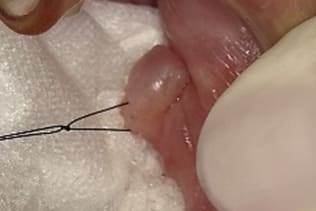

症例5 頬粘膜腫瘍(線維腫)の手術(60歳代 男性)

左側の頬粘膜腫瘍を主訴に当クリニックを受診された。

左側頬粘膜に境界比較的明瞭な弾性硬の腫瘍を認め、線維腫疑いの良性腫瘍と診断して腫瘍摘出術を施行した。

局所浸潤麻酔を行い、腫瘍に糸をかけ、十分にカウンタートラクションをかけた状態で、メスで腫瘍に沿って木の葉状に切開し、牽引しながらメスで周囲の結合組織と腫瘍の境界を鋭利に剥離する。切る感じではなくて削ぐ感じでメスを用いることが重要である。